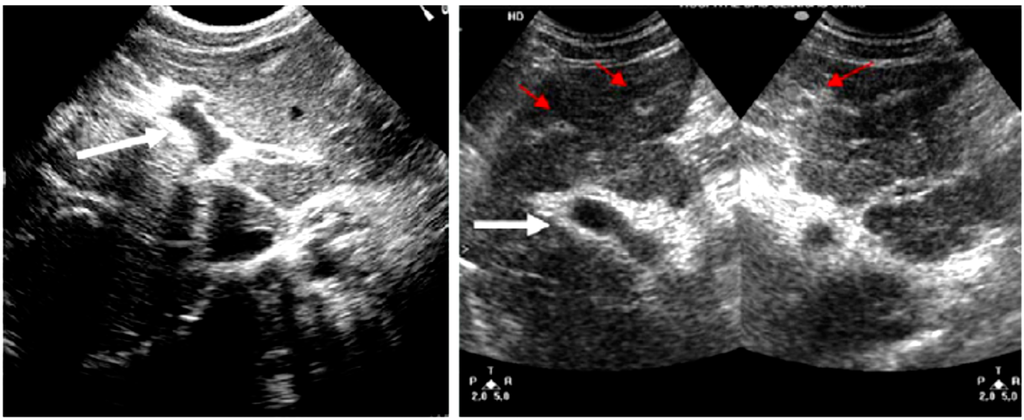

The critical stage in dengue occurs when the capillary permeability increases which leads to plasma leakage and therefore loss of plasma volume. The presence of pleural effusion and ascites are often used to determine the degree of plasma leakage. These are clinically detectable through physical examination techniques such as auscultatory percussion, and imaging techniques such as chest radiography, and also abdominal and thoracic ultrasonic imaging. Accordingly, several studies have used ultrasound as an aid for diagnosing dengue disease [18,19,20].

In the study by Srikiatkhachorn et al. [18] ultrasound has been employed to delineate the locations and the timing of plasma leakage in DHF. In the study, one hundred fifty-eight suspected dengue cases classified as DF, DHF, or other Febrile Illness (OFI) based on serology and evidence of plasma leakage including hemoconcentration and pleural effusion, were investigated. Ultrasound examinations of the abdomen and right thorax of patients were performed to detect ascites, thickened gall bladder wall, and pleural effusions. The results indicated that the timing of the plasma leakage was around the time of defervescence. The Pleural effusion was the most common ultrasonographic sign of plasma leakage while the thickening of the gallbladder wall and ascites were not associated as much in determining the plasma leakage. Significantly, plasma leakage of 12 out of 17 DHF cases who did not meet the WHO criteria for hemoconcentration signs was detected by ultrasound. The study concluded that ultrasound imaging is a useful tool for detecting plasma leakage in dengue infection.

Another study by Venkata et al. [19] was conducted to determine the importance of the ultrasound to clinical and laboratory profiles in diagnosing DF or DHF and to determine the usefulness of ultrasound in predicting the severity of the disease. One hundred twenty-eight suspected dengue patients (40 serologically negative for dengue fever and 88 serologically positive cases) were studied. Results of 32 patients from the 88 cases who were examined on the second to third day and repeated on fifth to seventh day showed that 100% had gall bladder wall thickening and pericholecystic fluid. Follow-up ultrasound on the fifth to seventh day showed ascites in 53%, left pleural effusion in 22%, and pericardial effusion in 28%. The results of the remaining 56 patients who were examined on the fifth to seventh day of fever for the first time showed that 100% had gall bladder wall thickening, 96% had ascites, 87.5% had right pleural effusion, and 66% had left pleural effusion. Contrary to the previous study, this study reported that thickened gall bladder wall, pleural effusion, and ascites should strongly favour the diagnosis of dengue fever.

In a separate work by Setiawan et al. [20], a study was conducted to examine the relationship between the clinical severity of 148 DHF patients (73 grades I and II; 75 grades III and IV) and their sonographic findings. Ultrasonography results revealed that the main features presented with grades I and II DHF patients were hepatomegaly 49%, ascites 34%, gallbladder wall thickening 32%, and pleural effusions 30%. On the other hand, the main features detected in DHF patients grades III and IV groups were pleural effusions, ascites and gallbladder wall thickening 95%, pararenal and perirenal fluid collections 77%, hepatomegaly 56%, and pancreatic gland enlargement 44%. The study concluded that ultrasound may be useful for early prediction of the severity of DHF.